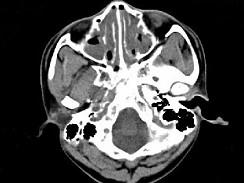

问题 男,14岁,持续性鼻塞、嗅觉减退,流脓涕数年,CT检查如图,最可能的诊断为 ( )

选项 A、恶性肉芽肿 B、上颌窦癌 C、鼻及鼻窦息肉 D、过敏性鼻炎及鼻窦炎 E、鼻炎及鼻窦炎

答案 E